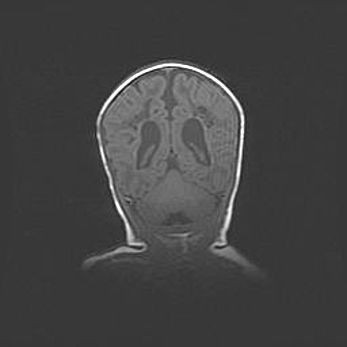

Церебральная ишемия II.

Возраст: 5 дней

Вес: 3400 г

Пол: женский

Окружность головы: 35 см

Срок гестации: 39 недель

Церебральная ишемия – это заболевание, характеризующееся недостаточностью (гипоксией) либо полным прекращением (аноксией) снабжения мозга кислородом по причине закупорки одного или нескольких сосудов. Это приводит к  что метаболическим расстройствам различной степени тяжести в тканях головного мозга, развитию коагуляционных некрозов и гибели нейронов.